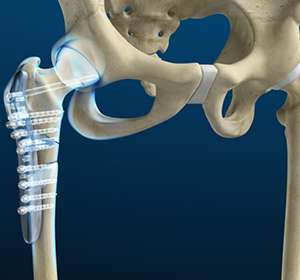

Revision hip replacement is a complex surgical procedure in which all or part of a previously implanted hip joint is replaced with a new artificial hip joint.

Femoral Nails

Femoral nails are metal rods used to align and stabilize fractured fragments of the femur or thigh bone. The rods are passed through the bone marrow at the center of the femur, across the fracture site.